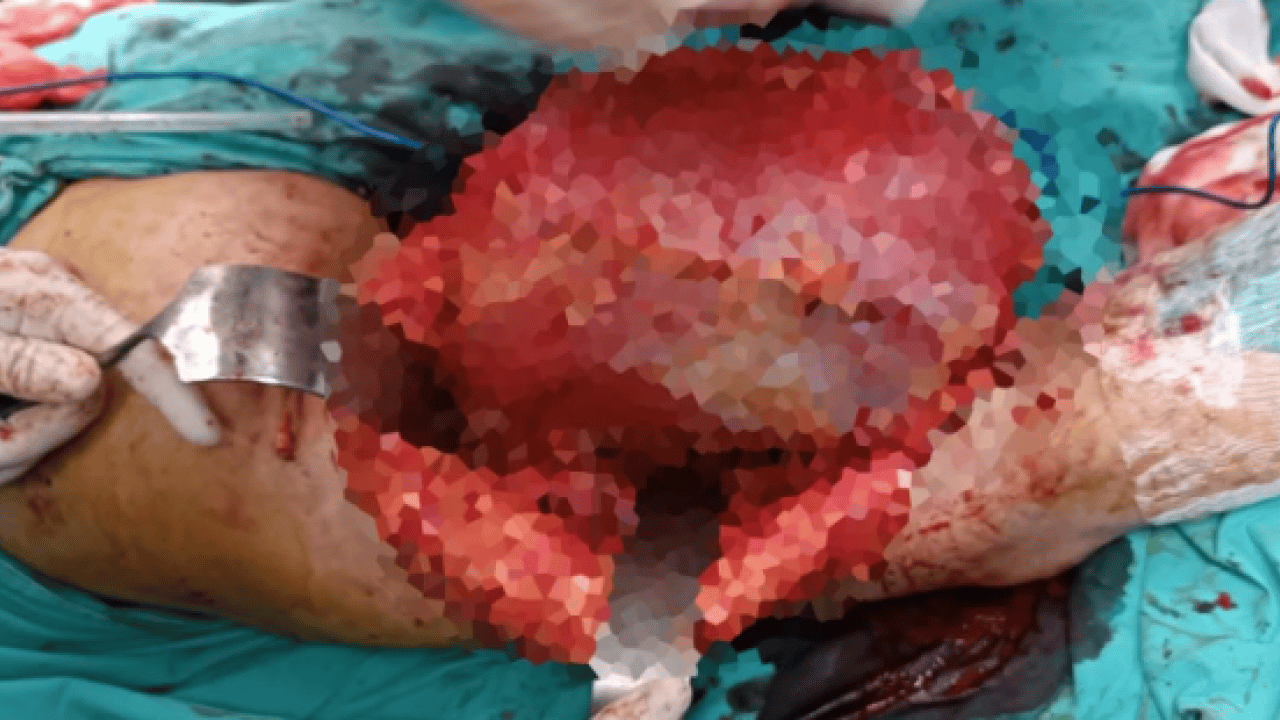

Diyarbakır Dicle Üniversitesi Hastanesi’nde, Mardin’den gelen H.T. isimli kadının bacağından 5 kilo 668 gramlık bir kitle çıkartıldı. Ameliyatı gerçekleştiren Prof. Dr. Emin Özkul meslek hayatındaki çıkarttığı en büyük kitle olduğunu söyledi.

Mardin’de yaşayan H.T. (42), 3 yıl önce sağ baldırının arka kısmında oluşan ve başlangıçta yumurta büyüklüğünde olan kitlenin zamanla büyümesi üzerine Dicle Üniversitesi Tıp Fakültesi Hastanesi Ortopedi ve Travmatoloji Bölümü’ne başvurdu. Muayenede yumuşak doku kitlesi olduğu değerlendirilen şişliğin alınması için Ortopedi ve Travmatoloji Anabilim Dalı Öğretim Üyesi Prof. Dr. Emin Özkul ve ekibi tarafından ameliyat kararı verildi. Yaklaşık 2 saat süren operasyonla kitlenin çıkarıldığı, kitlenin 5 kilo 668 gram geldiği belirtildi.

"Bu hasta da 3 yıl önce fark edilmiş küçük bir kitle, zamanla çok büyük boyutlara, yaklaşık 6 kiloya varan boyutlara varmıştı. Neredeyse bütün bacak boyu yayılan bir kitlesi mevcuttu. Bu kadar büyümenin şöyle sıkıntıları oluyor, kişinin bacağında, kolunda fonksiyon kaybına, yeri geliyor ekstremite kaybına, yani bacağını kaybetmesine yol açabilecek sıkıntılara yol açıyor."

"Küçükken bunlarla baş etmek daha kolay. Kişinin ekstremitesinde, bacağında, kolunda bir sıkıntı yaratmadan bunları telafi etmek, bunları alıp çıkartmak, ameliyatla bunları tedavi etmek daha kolayken bu boyutlara vardığında kişinin bacağında, kolunda fonksiyon kaybı, sakatlık riski çok yüksek oluyor. Bu sebeple küçükken önleminin alınmasında yarar var.” “Hastamızda yaklaşık olarak 3 yıl önce şikayetleri başlamış. Sonra zaman içerisinde hızla büyüyen bir kitleye sahipti. Şanslıydı ki herhangi bir sinirine zarar vermemişti. Hayatına fonksiyon bozukluğu olmadan devam edebilecek. Bölgemize yaşayan ve ülkemizde yaşayan herkese şunu söylüyoruz. Küçük de olsa yumuşak doku kitlelerini önemsemeleri ve uzman görüşü almalarını öneriyorum. Bu hastadan 5 kilo 668 gramlık bir kitle çıkarttık. Bu benim mesleki yaşamım boyunca çıkarttığım en büyük kitlelerden bir tanesiydi. Biraz daha büyük boyutlara varmış olsa kişinin bacağını kurtarma şansınız olmuyor. Bu sebeple bunlara dikkat etmek gerekiyor. Hızlı büyüyen bir kitleniz var ise, ağrısız da olsa mutlaka ve mutlaka tedavi için en yakın sağlık kuruluşuna veya bizim üniversitemizin polikliniklerine başvurabilirsiniz.”